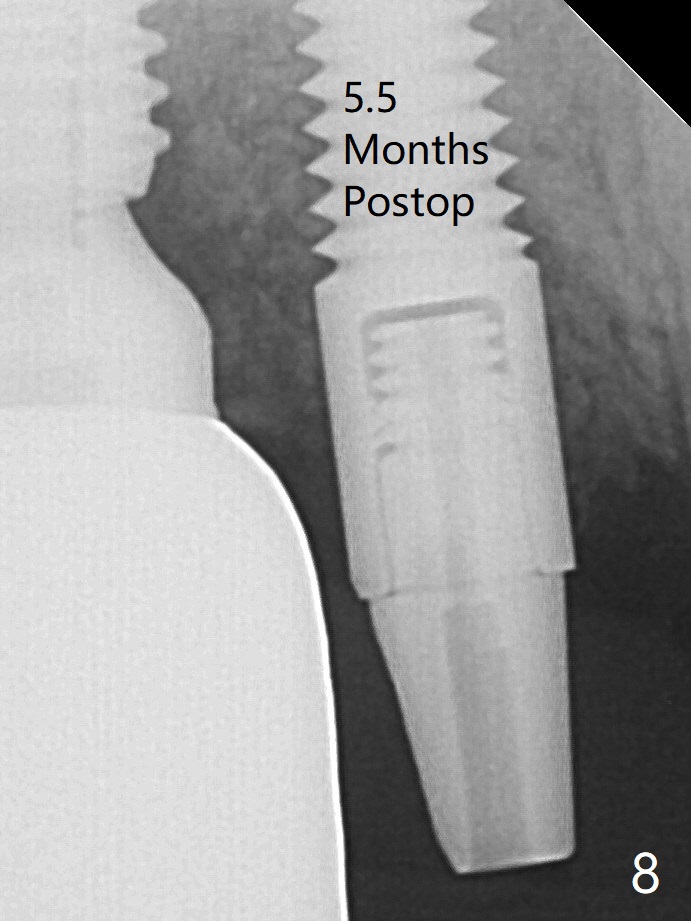

A 4x14 mm dummy implant is placed free hand (Fig.1). Following initial placement of a final 4x17 mm implant and bone graft (Fig.2 *), the crown and abutment of #3 and the guide are reseated for correct implant trajectory. The guide has to be removed for final depth control of the tissue-level implant. More bone graft is inserted mesial of #4 implant with a 3.5x5 mm abutment (Fig.3 *). The implant at # 4 seem to have osteointegrated, especially mesial, nearly 5.5 months postop (Fig.7,8 (BW)).